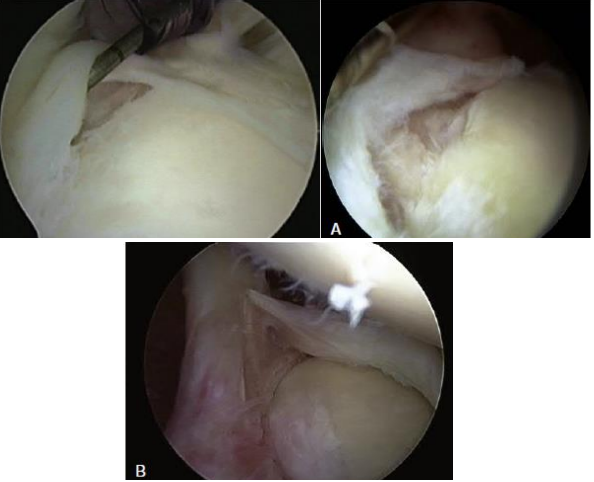

• Classificação artroscópica / morfológica de Snyder e Maffet (7):

Bizu: FRADE BALBI

• Tipo 1 ao 4 são os mais importantes

• Tipo 1FRAangeamento (aspecto degenerativo)

• Tipo 2DEstacamento (MAIS COMUM)

• Tipo 3 → Alça de BALde

• Tipo 4 → Alça de balde com extensão para ceps